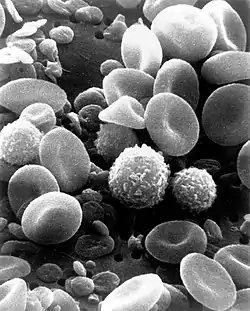

Ommatidia of Antarctic krill eye, a higher magnification of the krill's eye. SEMs cover a range from light microscopy up to the magnifications available with a TEM. Colored picture. SEM image of normal circulating human blood. This is an older and noisy micrograph of a common subject for SEM micrographs: red blood cells.